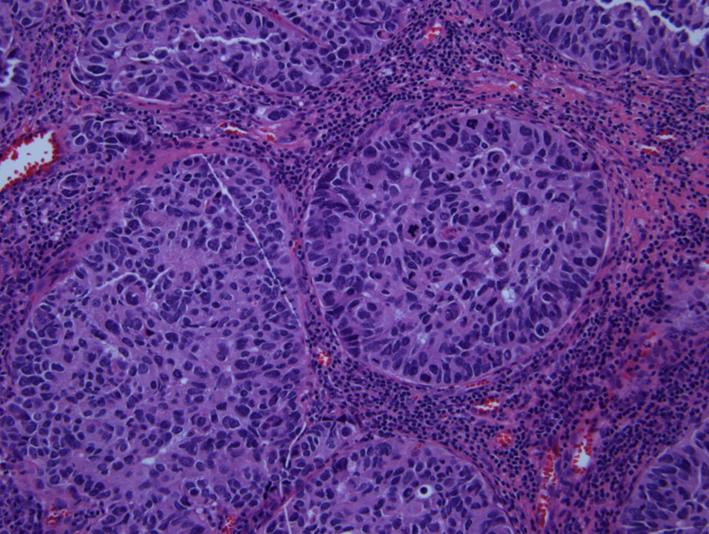

Pathologic examination of resected tumor showed large cells growing in sheets and nests (Fig. 3) There was numerous mitosis noted with abundant necrosis indicating a high-grade tumor (Fig. 4). Immunohistochemical stains performed show that malignant cells are strongly positive for cytokeratins CAM 5.2 (Fig. 5) and CK7 and negative for cytokeratin CK20. In addition, the malignant cells are strongly positive for synaptophysin and chromogranin (Fig. 6, 7), focally positive for TTF-1 (Fig. 8) and negative for PSA, HMB45 and GFAP. This was consistent with large cell neuroendocrine metastatic carcinoma with likely lung primary.

![]() Click for large image | Figure 3. H&E showing neuroendocrine features of organoid nesting, rosette-like structures and palisading pattern. |